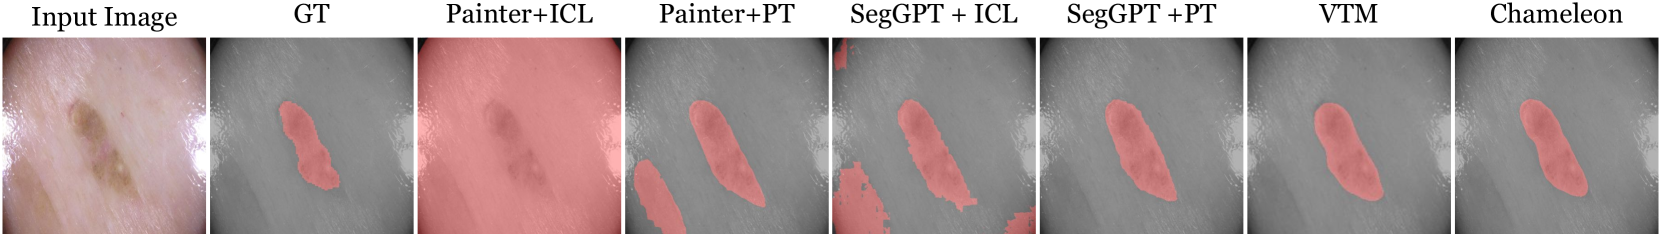

However, building a data-efficient generalist for dense visual prediction tasks, which involve high-dimensional outputs with vastly diverse structure and semantics [3], remains less explored. Most of the prior efforts for general dense visual prediction [33, 25, 11] mainly focus on unifying a range of pre-defined tasks into a single model, rather than generalizing to unseen tasks. Conversely, in-context learning approaches [61, 62] attempt to solve various tasks with few demonstrations by framing the dense prediction as an image-to-image translation problem. Yet, these methods often struggle to generalize to out-of-distribution tasks that have distinct output structures and semantics unseen during training, which limits their applicability to various real-world problems. Figure 2 highlights the necessity of a more flexible adaptation mechanism in building data-efficient vision generalists for arbitrary dense visual prediction.

We compare our model with three data-efficient generalist approaches: Painter [61], SegGPT [62], and VTM [24]. Painter and SegGPT can be used in unseen tasks with or without test-time adaptation through In-Context Learning (ICL) or Prompt Tuning (PT), respectively. Therefore, we evaluate Painter and SegGPT under both settings, where we apply SegGPT+ICL in only segmentation tasks since the model cannot handle the continuous label. For a fair comparison, we use the same support set for fine-tuning (VTM, Painter+PT, SegGPT+PT) and prompting (Painter+ICL, SegGPT+ICL). As all of these baselines do not support multiple input images, we apply them on tasks having a single input image.

Medical Semantic Segmentation

In this task, the model has to adapt to a huge domain shift from natural images in meta-training data to medical images. As shown in Figure 10 and Table 7, our model successfully adapts even with such domain gaps, while in-context learning methods struggle. Not surprisingly, with prompt tuning, Painter and SegGPT become competitive with our model, as they can address out-of-domain tasks with seen label semantics and structures. Still, Chameleon outperforms all the generalist baselines, showing its effectiveness.